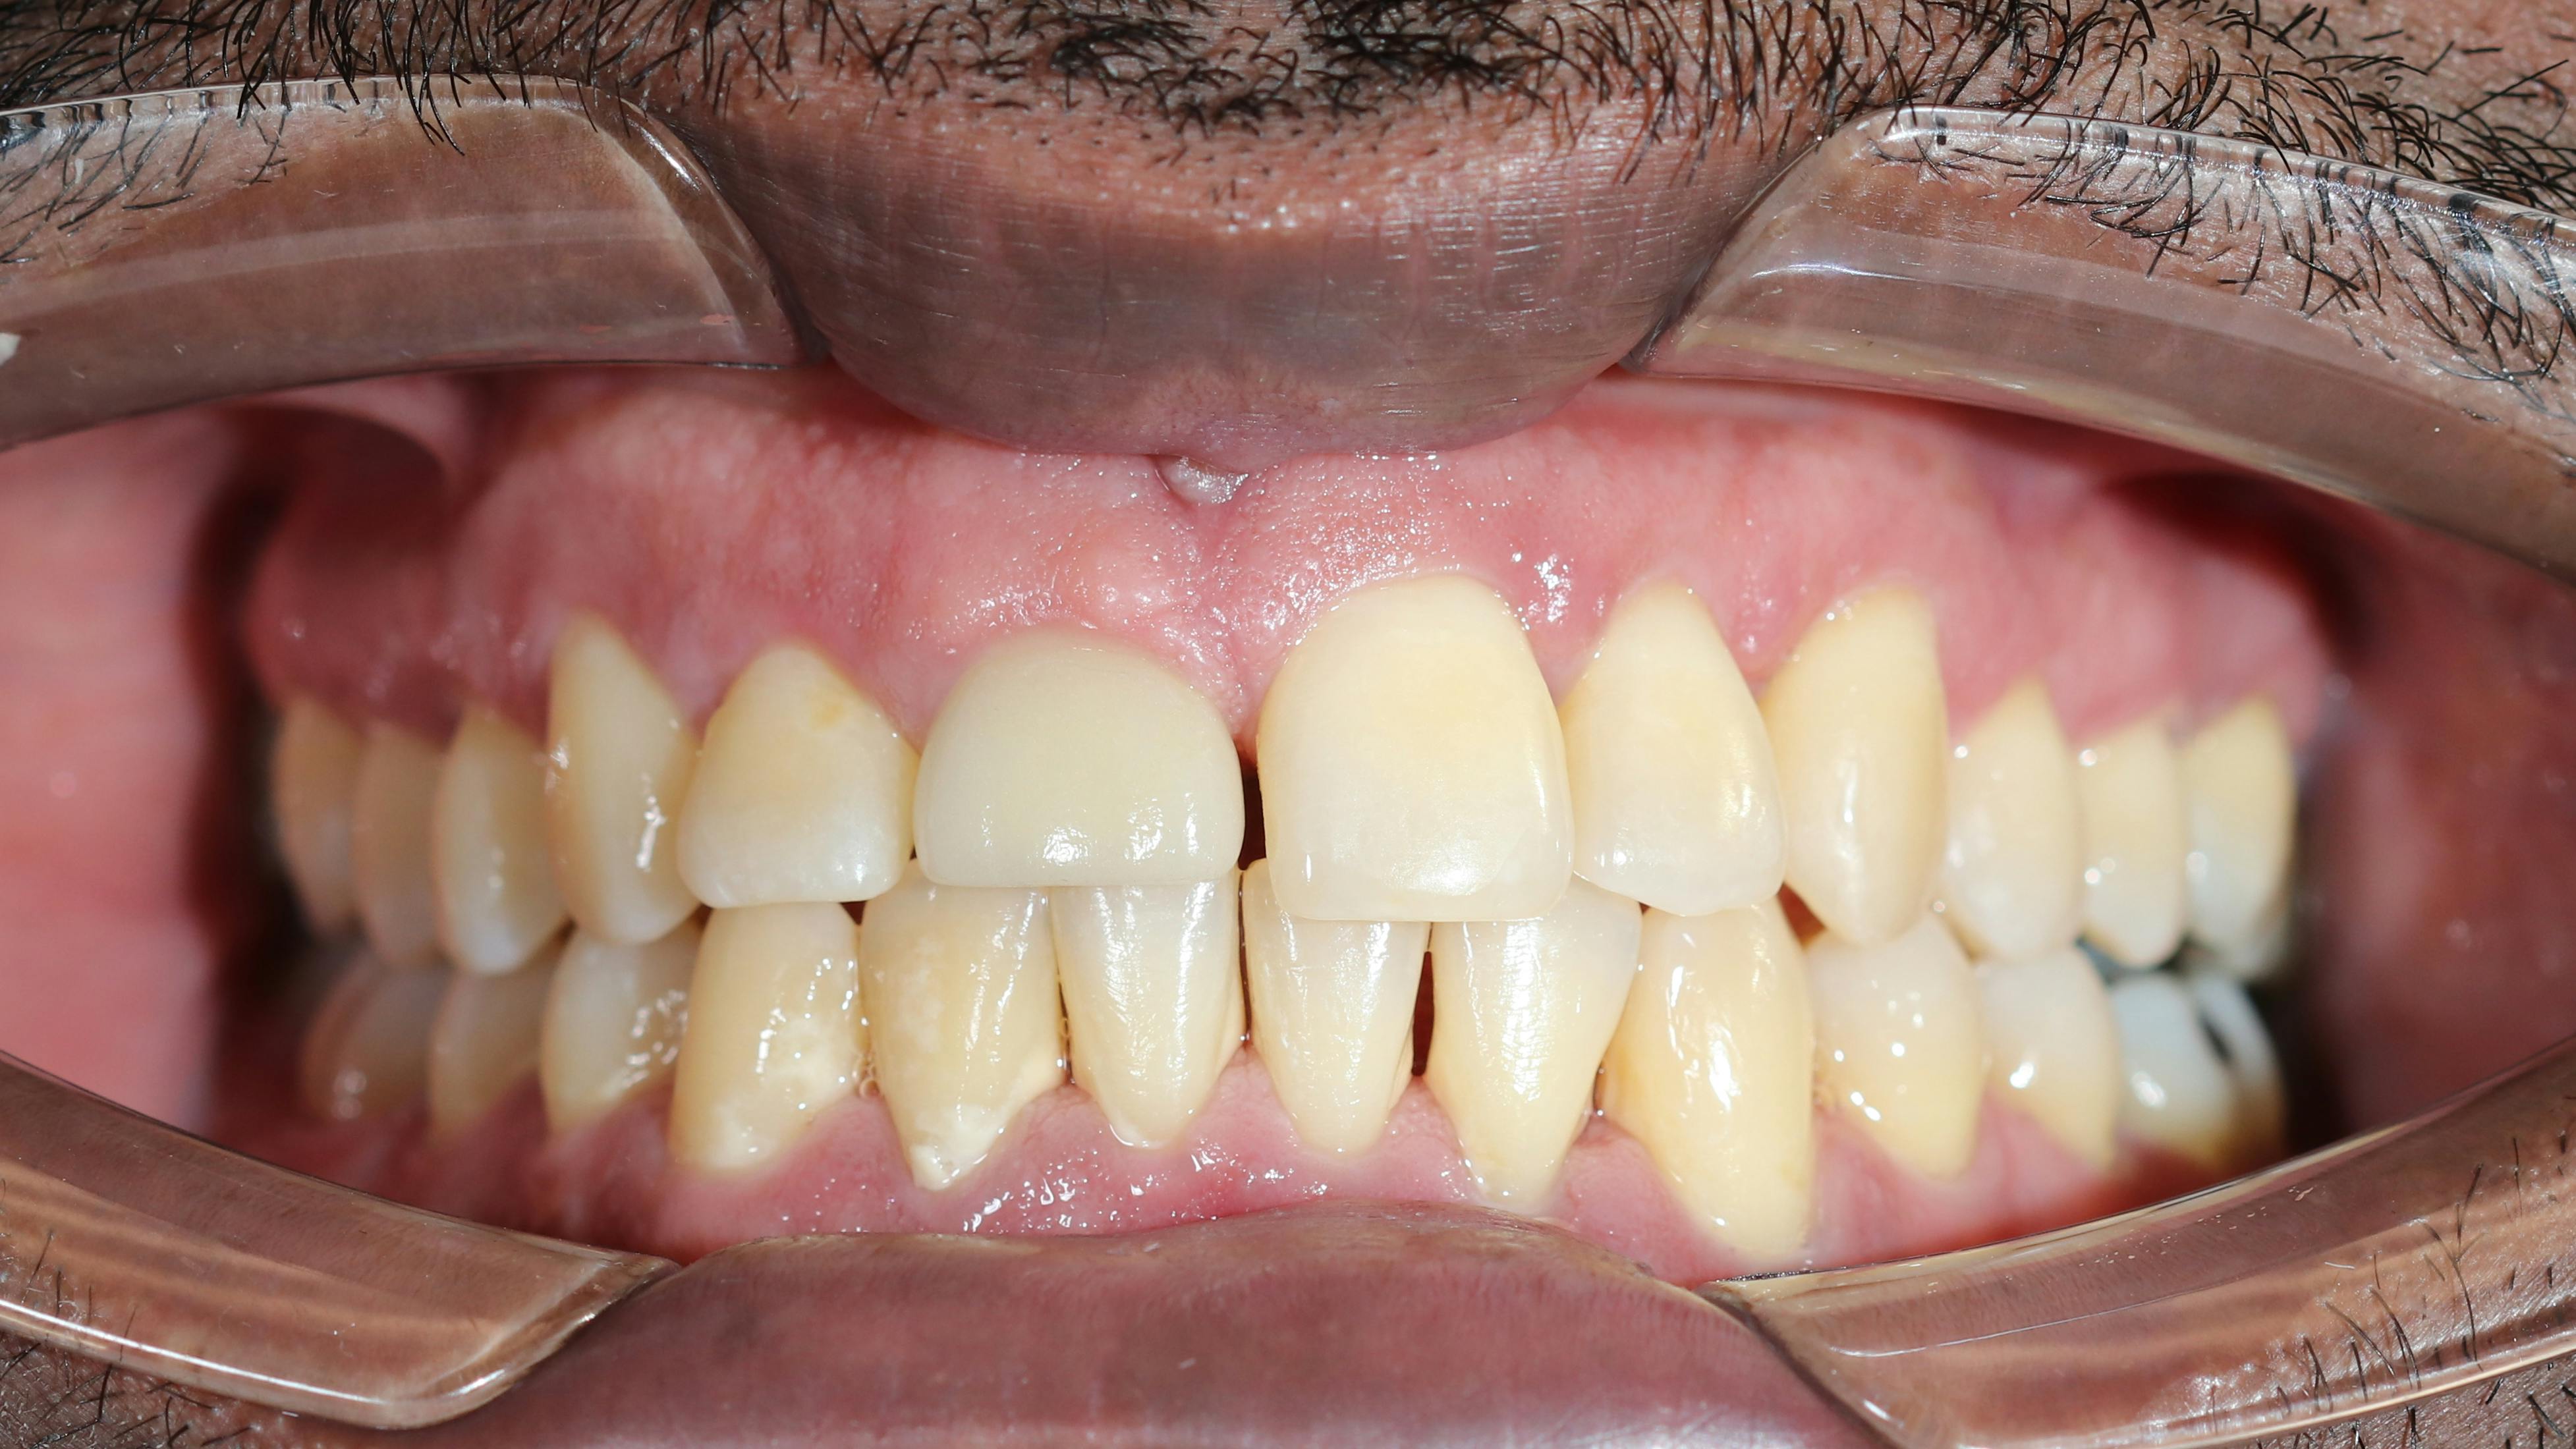

clinical photo of periodontal disease

Evidence increasingly links chronic periodontitis to Alzheimer’s disease through oral dysbiosis and inflammation. Periodontal pathogens like Porphyromonas gingivalis may contribute...

Jan. 5, 2026

Liudmila Chernetska/iStock/Getty Images Plus